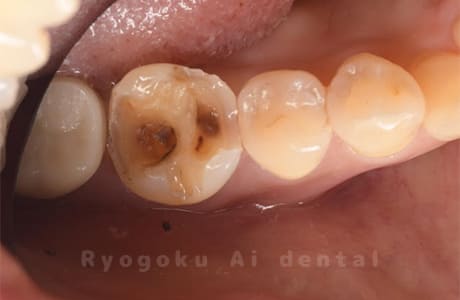

Case08

-

- 原因

- 虫歯

- 治療内容

- セラミックインレー

- 治療費用

- 77,000円

奥歯の黒い点が気になるということで来院された患者さんです。白い詰め物を外したところ、虫歯が中で大きく広がっていたため、患者さんと相談し、セラミックインレーで治療を行いました。

<リスク・副作用>

過度の咬合や衝撃で割れることがあります。